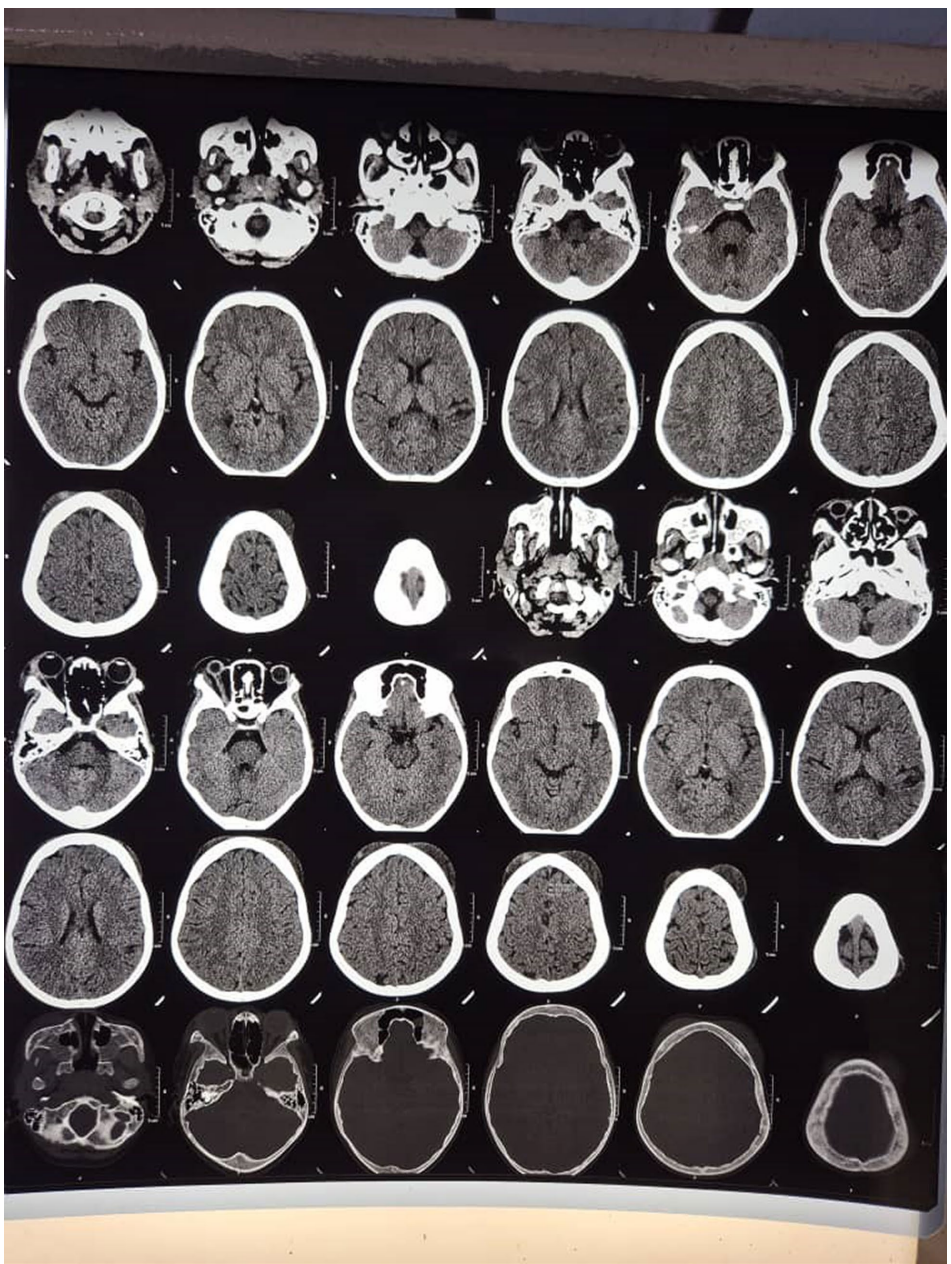

来自乌干达的研究团队在《Journal of Medical Case Reports》报道了一例极具教学意义的病例:一名未接受羟基脲治疗的9岁SCD男性患儿,突发多发性头皮血肿并迅速进展为右眼OCS,伴随中性粒细胞增多的轻度贫血(血红蛋白8.9 g/dL)。通过非增强头颅CT确诊为双侧额部帽状腱膜下血肿合并右眼眶受累,关键影像显示血肿最大达7×7 cm但无颅骨侵犯

患儿表现为4处波动性头皮血肿(最大7×7 cm)伴右眼突眼,角膜下1/3荧光染色阳性但视力未受损。与创伤性血肿的关键区别在于无外伤史及CT显示的特征性骨髓腔扩张。